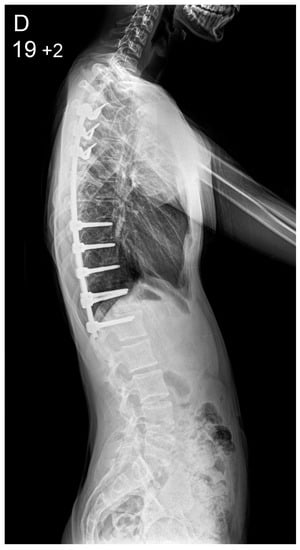

Figure 1.

Patient aged 15 years and 9 months with a right thoracic AIS producing thoracic translocation and listing of the trunk to the right, as well as thoracic flat back producing negative global sagittal balance of the spine and compensatory cervical kyphosis (A,B). The patient underwent posterior scoliosis correction using the AS technique which restored segmental and global coronal/sagittal spinal balance at latest follow-up (age 18 years and 8 months) into adult life (C,D). Clinical photographs demonstrate excellent correction of the coronal deformity and associated rib hump after scoliosis surgery (E–H).